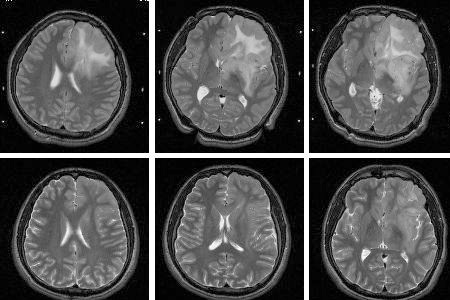

頭部腫瘤的症狀:早期發現與診斷的重要性

頭部腫瘤是一種嚴重的疾病,它可能在早期就表現出一些症狀。了解頭部腫瘤的症狀以及如何早期發現和診斷是至關重要的。本文将詳細介紹頭部腫瘤的症狀,以及爲何早期發現和診斷對于治療和預後具有重要意義。

早期發現與診斷的重要性

早期發現和診斷頭部腫瘤對于治療和預後具有重要意義。在早期階段,腫瘤通常較小,生長緩慢,因此治療效果更好,生存率更高